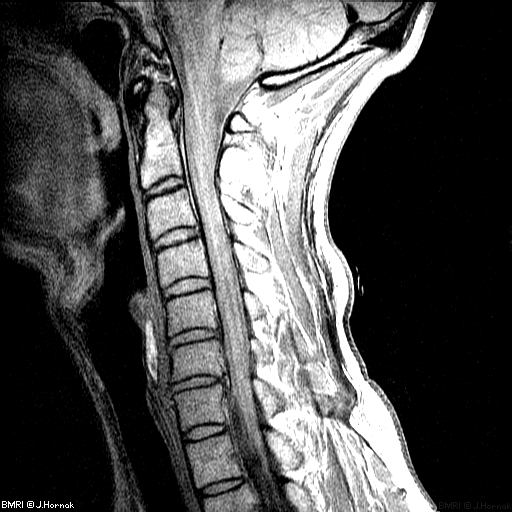

Для диагностирования деформирующего спондилеза проводится ряд инструментальных исследований — рентгенография, МРТ, КТ, электромиография, миелография. Практикуется консервативное лечение, но при развитии серьезных осложнений пациентам показано хирургическое вмешательство.

После осмотра пациента, выслушивания жалоб и изучения анамнеза проводится инструментальная диагностика. Наиболее информативна рентгенография, позволяющая оценить состояние костных, мягких и хрящевых тканей. Для подтверждения диагноза может потребоваться проведение компьютерной томографии для осмотра плотных структур шейного отдела, МРТ для визуализации мягких тканей. Электромиография назначается для исследования нервной проводимости. Результаты лабораторных анализов крови и мочи позволяют оценить общее состояние здоровья пациента, выявить нарушения обмена веществ.

Если нет возможности проведения КТ и МРТ, то используется миелография. В позвоночный канал нагнетается воздух или вводится контрастное вещество, а затем делается серия рентгенологических изображений.